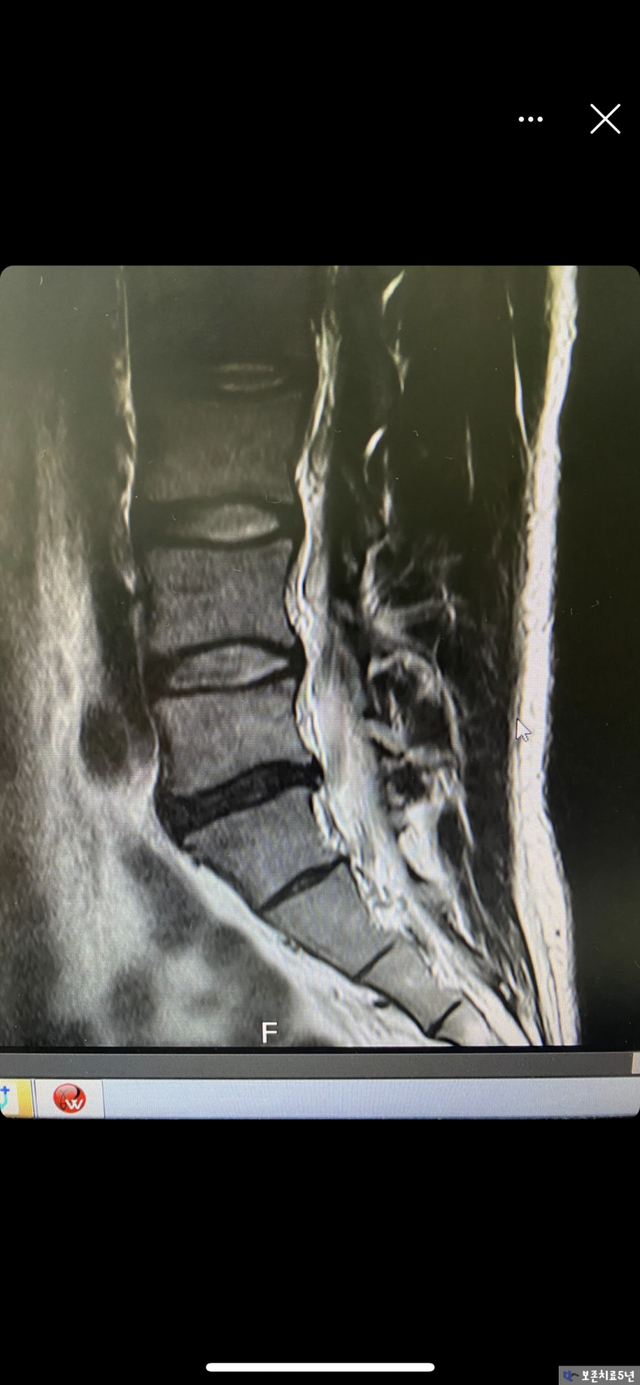

이렇게 버티다가 결국 원인을 못 잡으니 결국에는 취준 준비하다가 허리디스크로 입원하고 시술했다.

시술하니 진짜 허벅지 저림, 등 목쪽 불편하고 땡김 이런 게 싹 없어졌는데 딱 2주되니깐 그대로 돌아오더라.

3. 젊은사람이 수술 및 시술을 하면 안되는 이유

이러니깐 내가 척추전문병원을 정말 혐오한다. 친절과 가식으로 MRI 비용과 도수치료 비용 시술 1주일 동안 몇 백만원을 쓰게 만드는 공장 같은 시스템.

내가 수술과 시술을 비추천 하는 이유가 딱 이거다.

허리통증의 원인은 결국 근육 불균형으로 인한 보상작용을 통해 척추가 일자목, 일자등, 일자허리로

변하고 이 상태로 격한 운동 및 장시간 앉아있으니 계속된 압력이 디스크를 미는 것이다. 이 부분이 가장 중요.

디스크를 수술하거나 시술한다하더라도 재발되는 이유는 원인은 우리 몸에 올바른 움직임이 나오지 않고, 필요한 근육이 활성화 되지 않아

척추질환을 얻게 되었는데 통증만 줄인다고 해결되는 것이 아니기 때문이다.